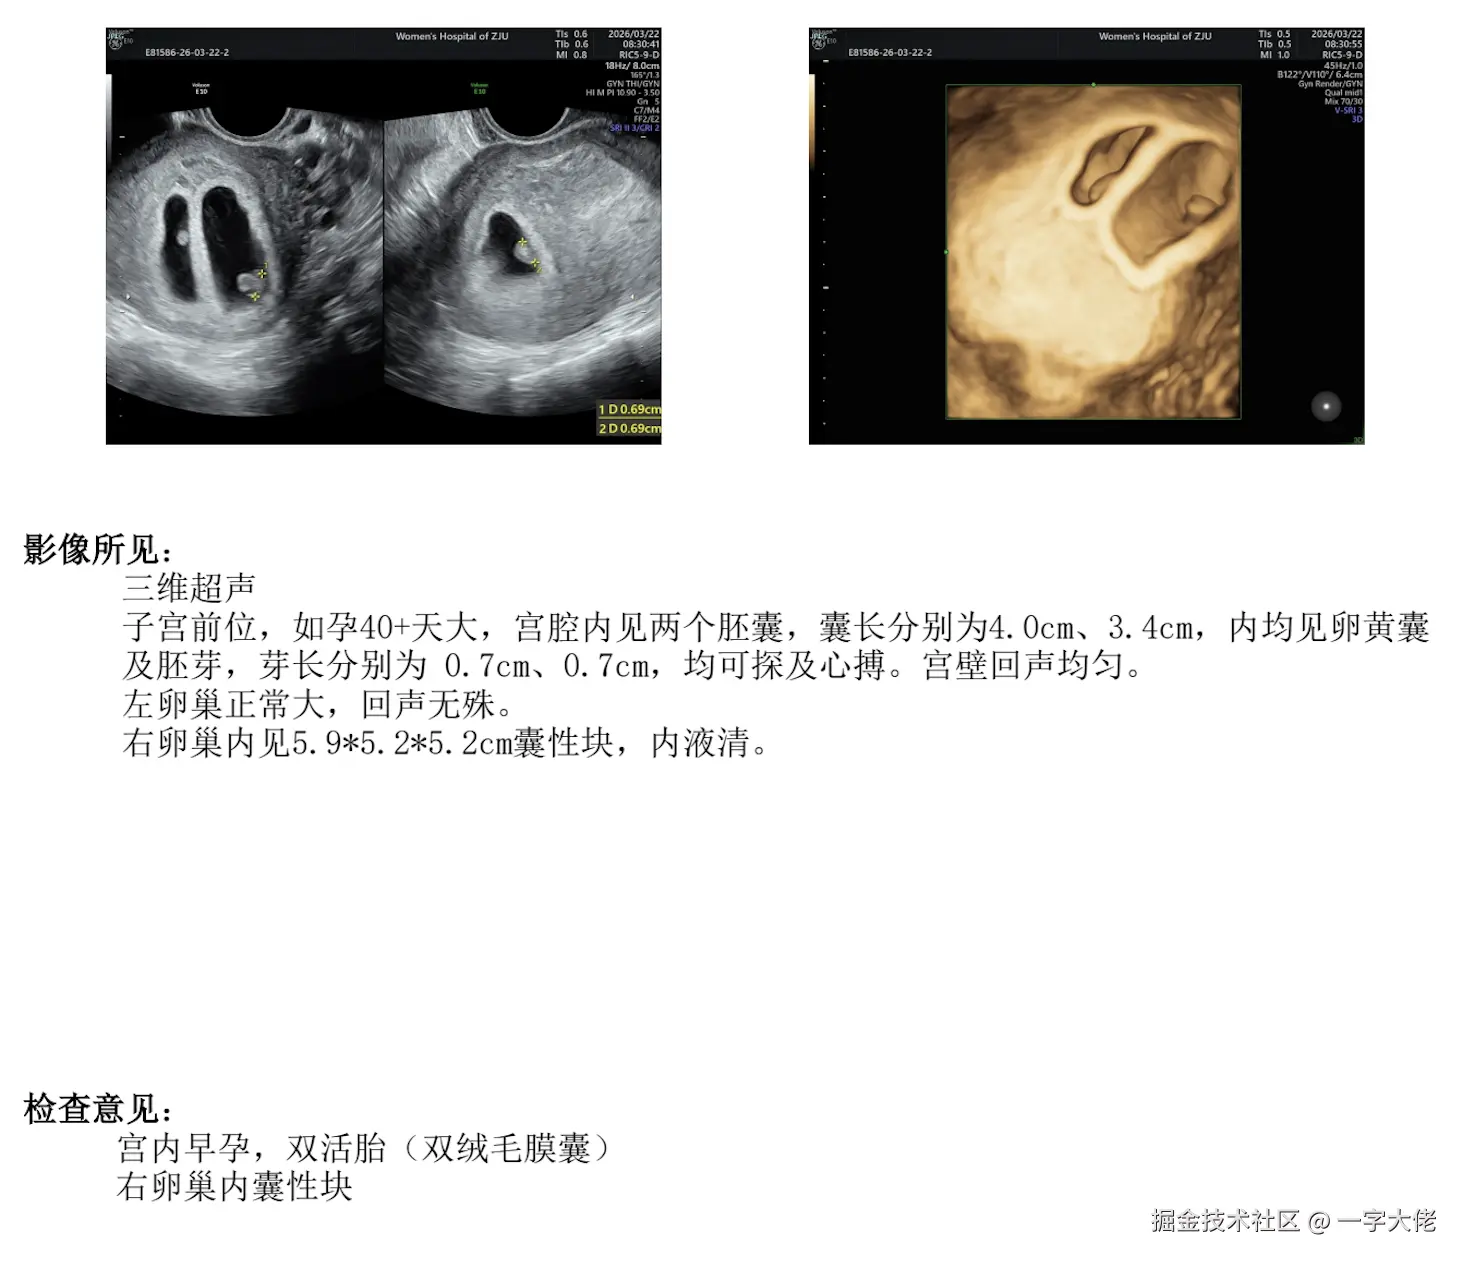

Hello World

各位叔叔阿姨好呀